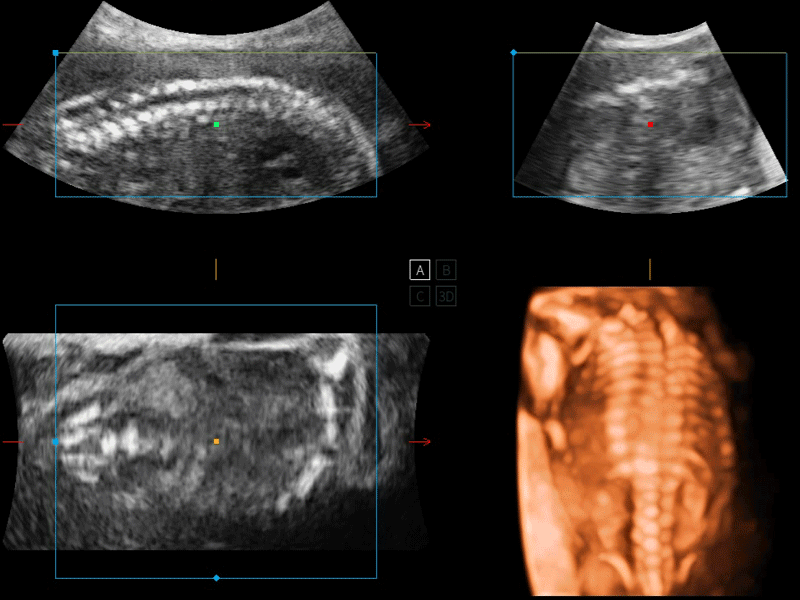

S-Live 高分辨率容积成像

通过仿真成像技术对3D/4D立体数据进行渲染,多种初始光源位置可选,并支持轨迹球360°光源位置自由调节,清晰显示不同方位容积图像细节。